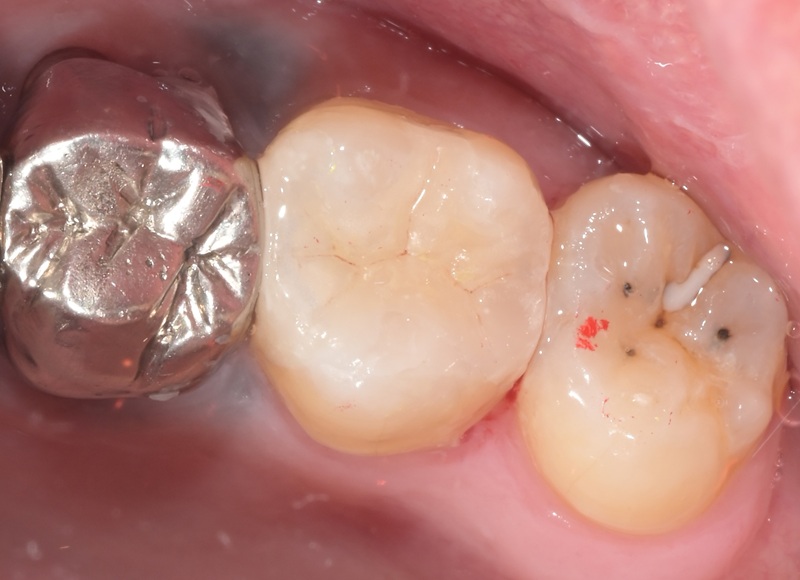

Case2

術前

術中

術後

| 治療名 | セラミックインレーによる虫歯の再治療症例 |

|---|---|

| 治療説明 |

過去に治療された銀歯が外れたとのことで来院されました。内部には古い接着剤の劣化と虫歯の再発が見られたため、しっかりと虫歯を除去し、セラミック製の詰め物(インレー)で再修復を行いました。 セラミックインレーは、天然歯に近い色調と自然な透明感を持っており、見た目が気になる部位にも適しています。 |

| 治療回数・期間 | 2回 |

| 副作用とリスク | ・保険診療の銀歯に比べて費用が高くなります。 ・治療直後は一時的に知覚過敏のような症状が出ることがありますが、ほとんどの場合は数日〜1週間程度で落ち着きます。 |

| 料金(税込) | 77,000円 |